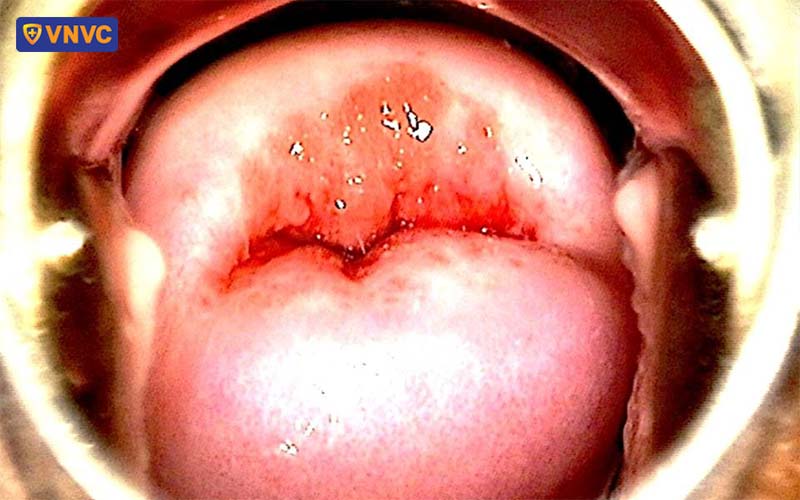

Khi mắc bệnh, người bệnh sẽ có những tổn thương đặc trưng như nốt u nhú, nốt sần xung quanh cơ quan sinh dục (môi âm hộ hoặc ở cửa âm đạo, cũng có thể ở xung quanh hoặc bên trong hậu môn), miệng và vòm họng kèm theo cảm giác đau rát, khó chịu. Những triệu chứng này sẽ xuất hiện sau vài tuần nhiễm bệnh nhưng cũng có một số trường hợp kéo dài đến nhiều năm. Trong thời gian ủ bệnh, người bệnh vẫn có khả năng lây nhiễm virus sang những người xung quanh.